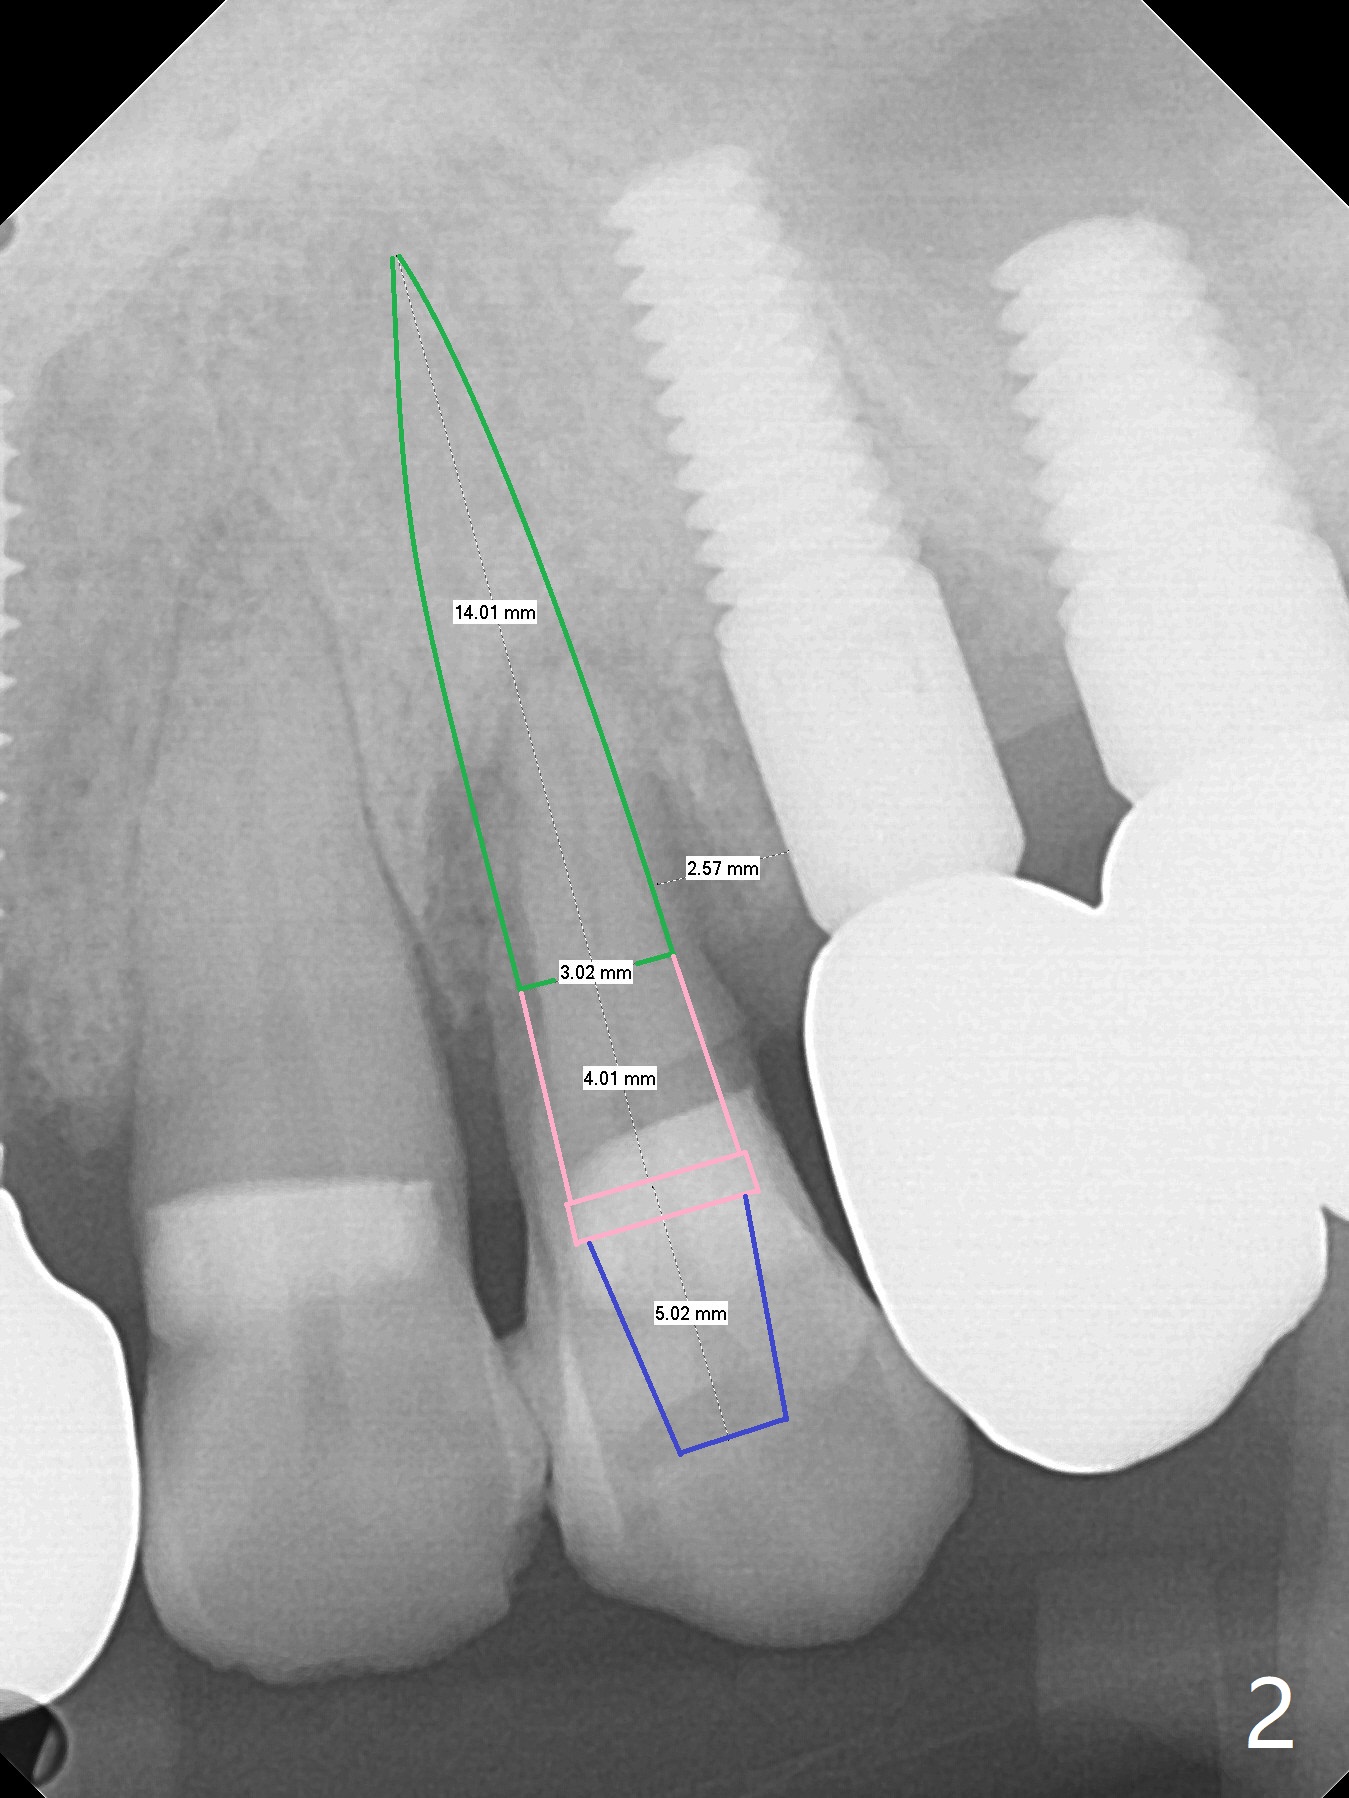

A 66-year-old man agrees to extract #12 for implant immediate post #10 implant crown cementation (Fig.1). Because of the narrow mesiodistal space, either a 1-piece (Fig.2) or 3.5 mm 2-piece (Fig.3) implant will be placed.